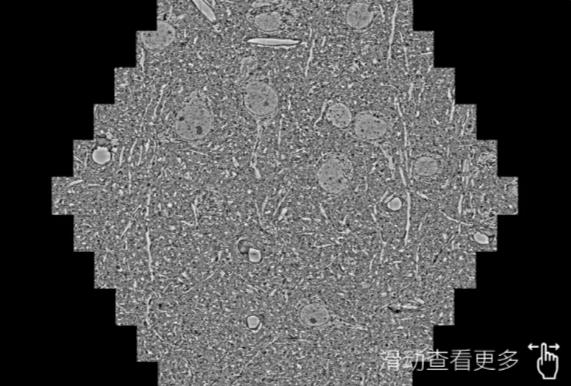

鼠脑切片。左图使用孝感蔡司孝感扫描电镜MultiSEM706对165μmx143pm面积区域成像,耗时仅需1.5秒。右图为鼠脑切片中30μm区域放大效果。样品由芝加哥大学B.Kasthuri提供。

使用蔡司高速孝感扫描电镜MultiSEM对1mm²人脑皮层组织进行高分辨成像,并对其中的各种细胞结构进行三维重构分析。左图展示了2x3mm²组织平面中锥体神经元的三维重构效果。右图显示了局部体积神经元三维重构。图像由哈佛大学chtman实验室提供,渲染图由D. Berger 制作。